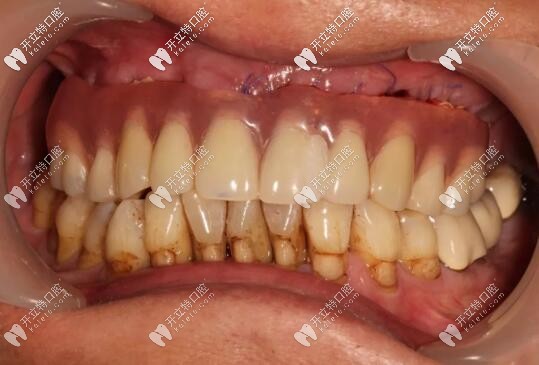

半口種植牙前

西安美奧牙科all-on-6種植牙案例

修復(fù)前

病史上頜于10年前因牙周病導(dǎo)致的牙齒缺失,曾做過(guò)可摘戴活動(dòng)義齒修復(fù)。